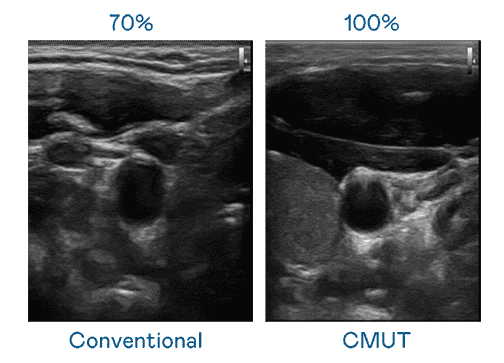

CMUT 技术是一种用电容式微机电元件来产生超音波讯号的技术。。。与传统 PZT 压电式技术相比,,,CMUT 频宽增加 30%,,更宽频的超音波讯号让影像解析度大幅提升,,是实现高影像品质医疗超音波扫描、、、促进精准医疗发展的关键技术。。

大频宽带来超清晰影像

超音波影像的解析度高低,,,首先取决于探头能发出的讯号频宽。。。z6mg·人生就是博 CMUT 可提供高清晰的超音波讯号,,,提供高频宽、、高灵敏度、、、影像纹理细节更高的超音波影像,,协助医护人员缩短影像判读时间及利用精准的医疗影像进行诊断。。